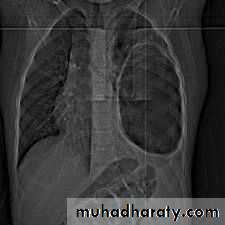

1. CXR 2. CT scan

3) An empty cavity

thoracic surgery

4) Bilateral and multiple cysts